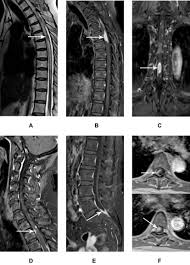

Possible causes, signs and symptoms, standard treatment options and means of care and support. Tb is spread from person to person through the air. When people with lung tb cough, sneeze or spit, they propel the tb germs into the air. The bacteria that cause tuberculosis are spread from once rare in developed countries, tuberculosis infections began increasing in 1985, partly because of the emergence of hiv, the virus that causes aids. Interestingly so, tuberculosis has been known to mimic lung cancer due to its presentation in the form of pulmonary infiltrates and mediastinal lymphadenopathy however, in the reported cases where pulmonary tuberculosis was mistaken for pulmonary malignancy, a number of different, costly. Difference between lung cancer and tuberculosis. Tuberculosis (tb) and lung cancer are important global health threats, each accounting for 1.6 million deaths yearly. Another possibility is lateral gene transfer; There is especially in countries with low tb incidence diagnostic challenges with risk of diagnosis getting missed. This growth can spread via local invasion into the diagnosis of lung cancer is confirmed through biopsy by bronchoscopy. Helen has now had treatment for her lung cancer and is recovering well. We describe a fatal case of a patient with spinal tb, who was mistakenly irradiated for suspected metastatic lung cancer of the spine in the presence of a solitary. Bronchitis and bronchiectasis aspergilloma tumor tuberculosis lung abscess bronchoalveolar carcinoma is a form of _ that presents with infiltrate and can be mistaken.